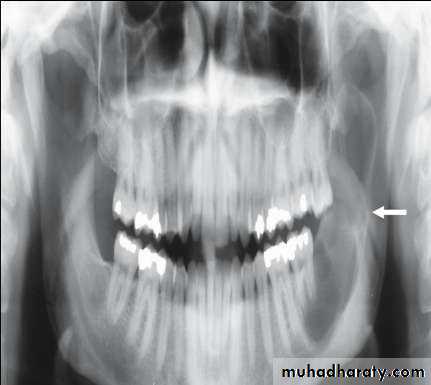

• Radiography:• Uni or Multilocular radiolucent areas

• Soap bubbles

• Copyright 2003, Elsevier Science (USA). All rights reserved.• Ameloblastoma

• Radiography:

• Soap bubbles appearance